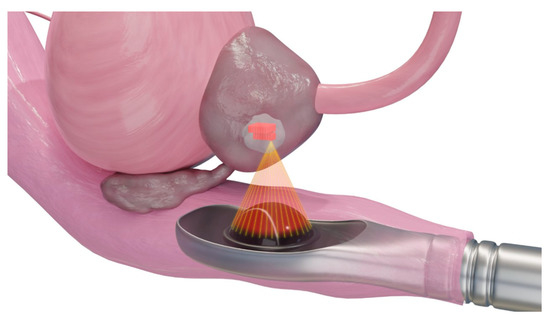

3.6. High-Intensity Frequency Ultrasound